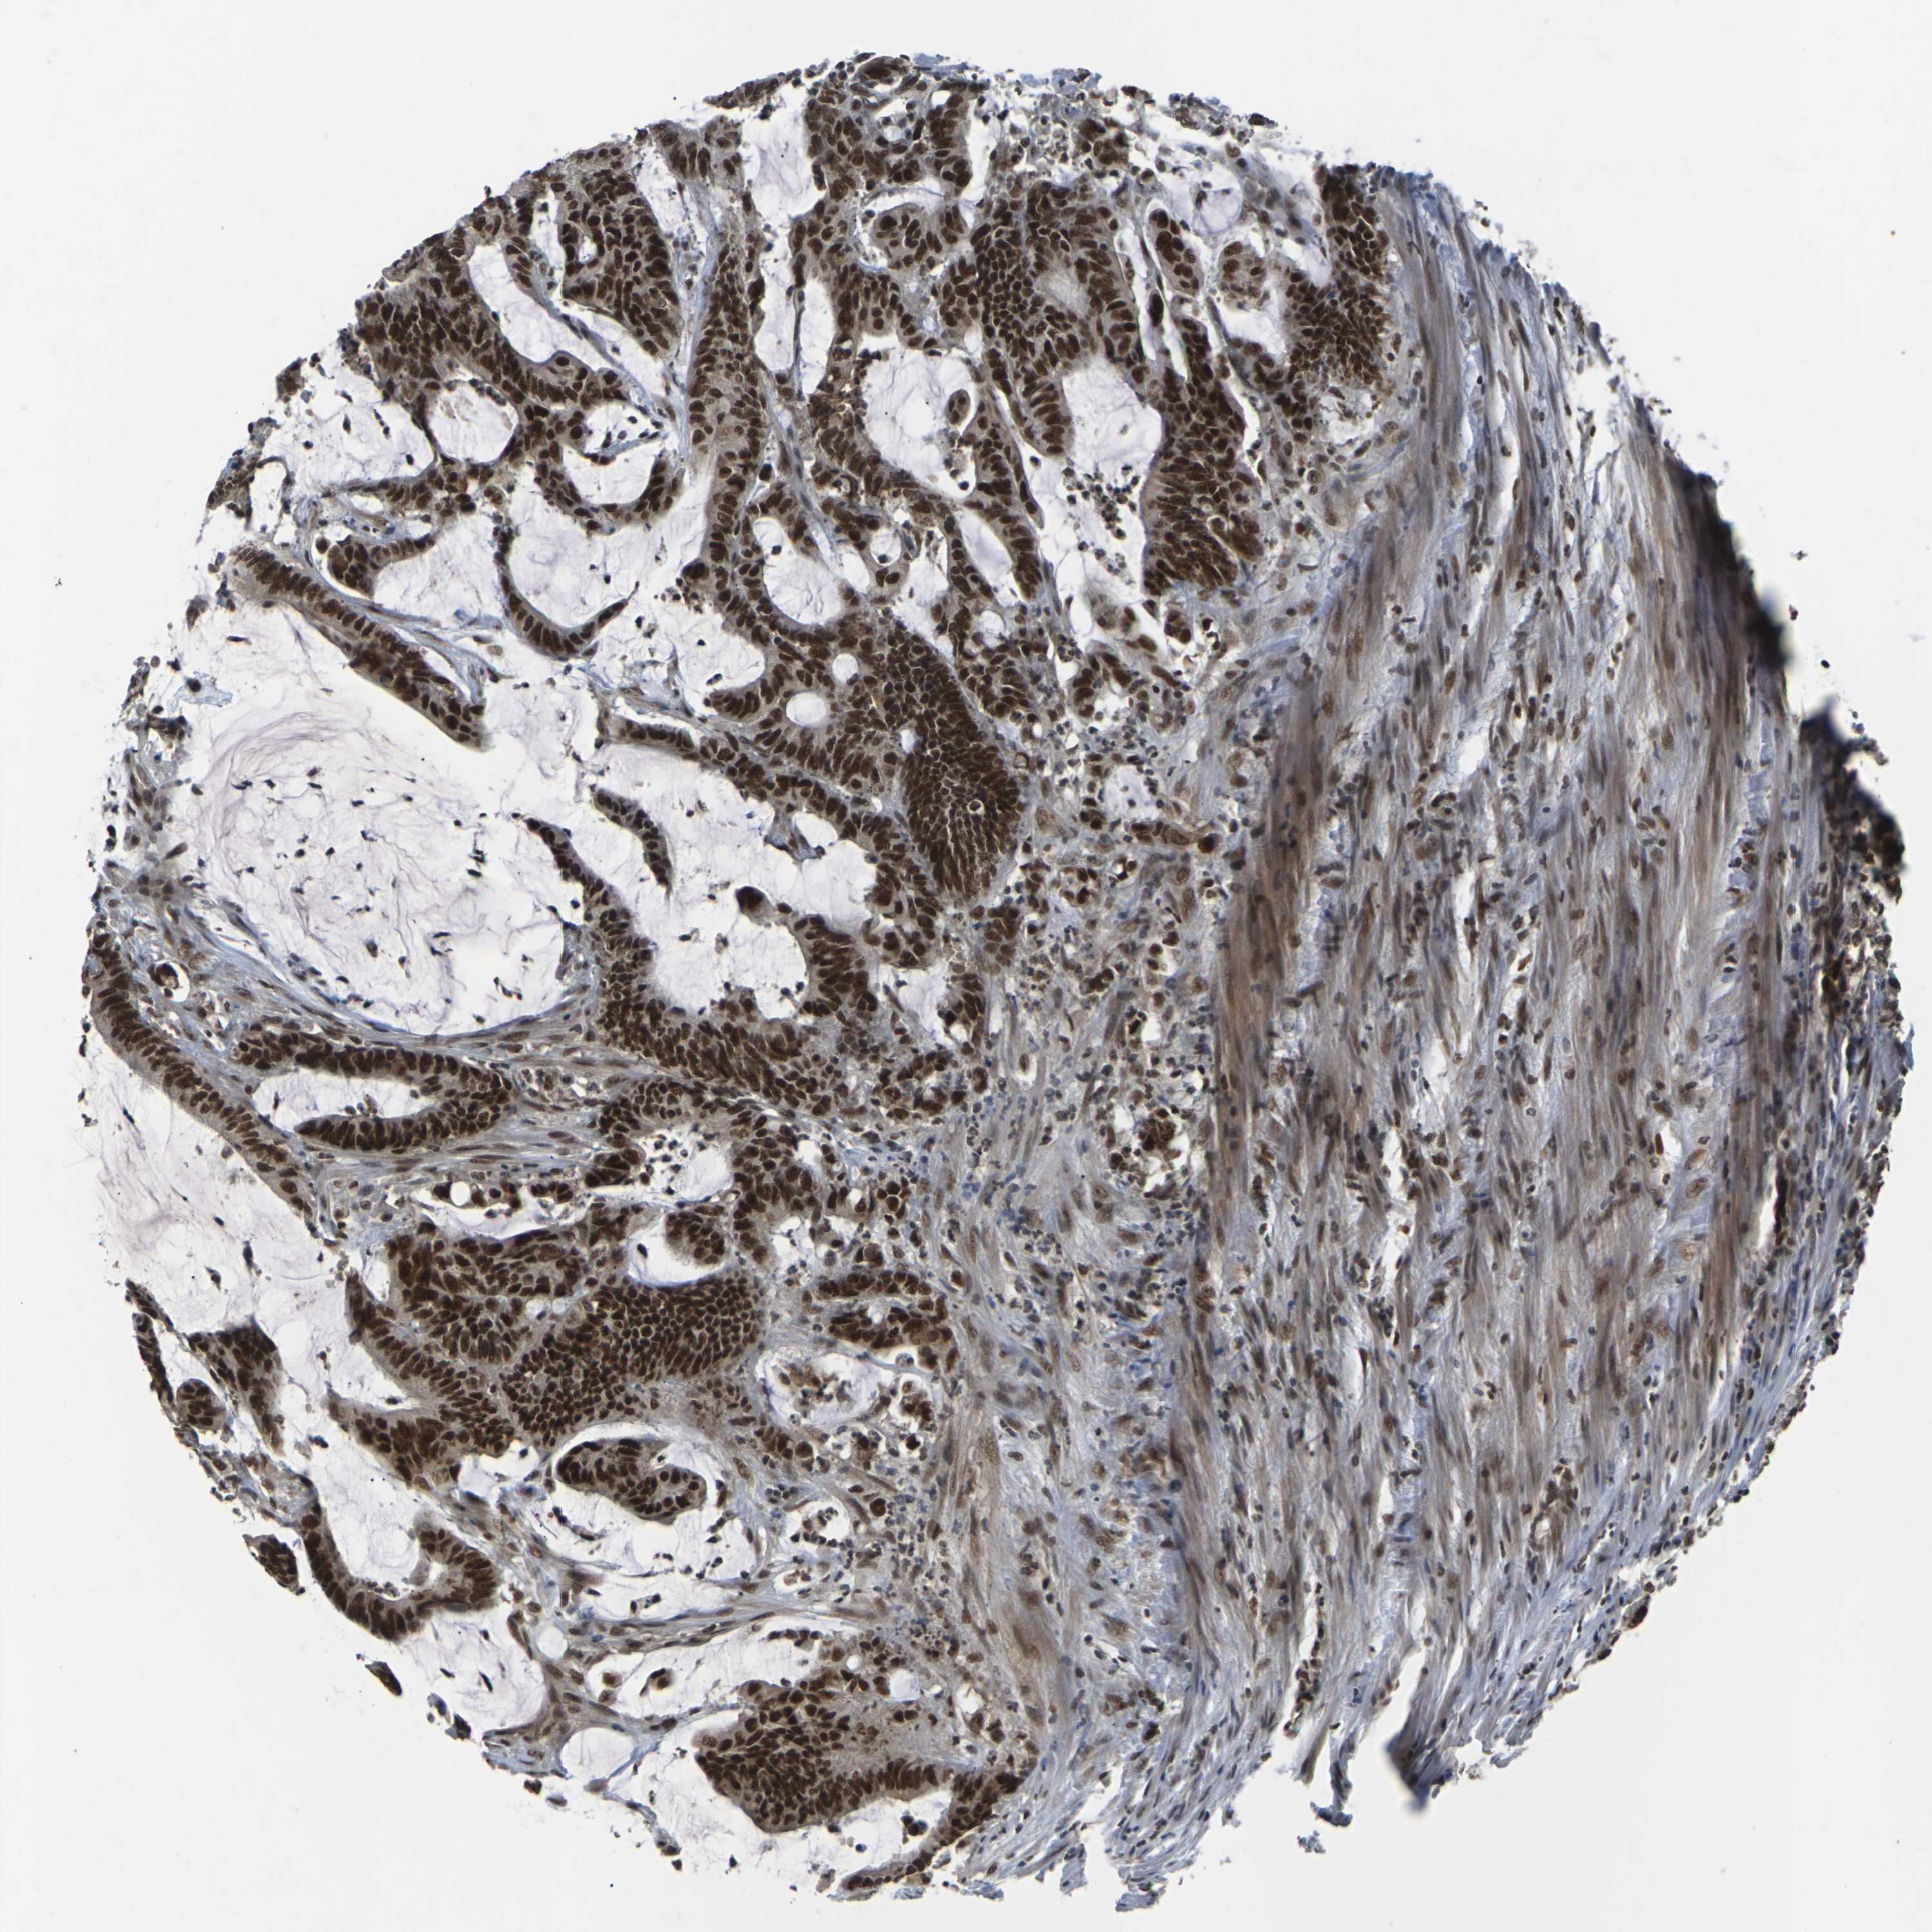

CANCER COLORECTAL CANCER Show tissue menu

Colorectal cancer

Human cancer

Colon adenocarcinoma